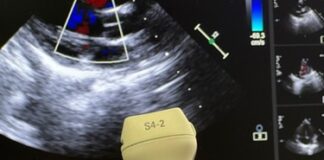

Progetto Pulcino – Donazione sonda ecocardiografica Philips S4-2 e guanti ZAKY

REGGIO EMILIA - Progetto Pulcino, grazie ad una raccolta fondi ideata e promossa da Riccardo Benetti de La Casa del Miele di Reggio Emilia,...